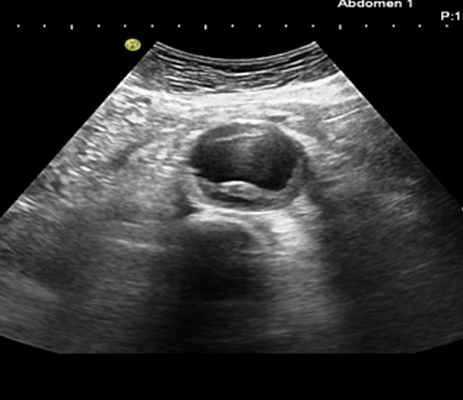

При расслоении III типа проводится УЗИ брюшной аорты.

У большинства людей с аневризмой брюшной аорты нет никаких симптомов, и АБА случайно выявляют во время ультразвукового исследования органов брюшной полости (УЗИ органов брюшной полости) или компьютерной или магнитно-резонансной томографии, выполняемой по другим показаниям. В настоящее время рекомендовано мужчинам в возрасте от 65 до 75 лет, которые когда-либо курили, проходить медицинский осмотр и УЗИ обследование для выявления AA.

Риск разрыва АБА зависит от размера аневризмы и от скорости ее расширения. Даже небольшая АБА, увеличивающаяся на 0,5 см или более в течение шести месяцев наблюдения, имеет высокий риск разрыва. У курильщиков и людей с неконтролируемой артериальной гипертензией рост АА обычно бывает более быстрым. Появление таких симптомов:

— боли в животе и спине,

— пульсация в животе